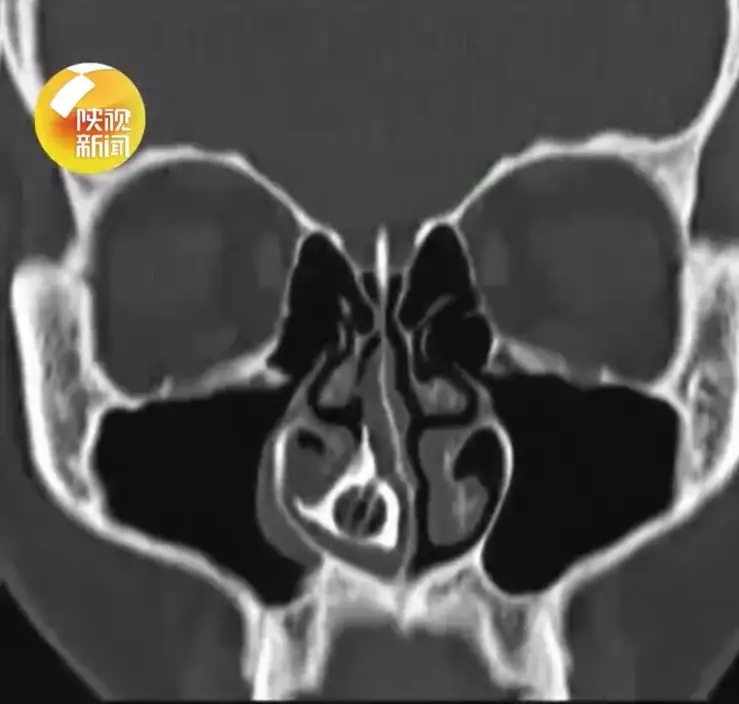

照CT揭真相 鼻腔異物已鈣化成「鼻石」

當日,醫生檢查時發現小敏鼻腔深處疑似存在異物,隨後安排電腦掃描(CT)檢查,結果清楚顯示鼻腔內有一個邊界清晰的球狀物體。由於異物滯留時間過長,已與周邊組織嚴重嵌頓,甚至形成堅硬的鈣化結石(鼻石)。手術過程中,醫生需先將結石擊碎,才能分塊取出「元兇」,最終取出一顆紅色中空的圓形串珠,推測來自手串或飾物配件。

醫生指出,異物長期滯留後會被分泌物及組織包裹,逐漸鈣化形成「鼻石」,加上位置隱蔽,若未作詳細內視鏡或影像檢查,容易被誤診為普通鼻竇炎或慢性鼻炎。醫生對此提醒,若病人長期出現單側鼻塞、流膿涕且反覆發作,應提高警覺,及早進行進一步檢查,以免延誤診治。